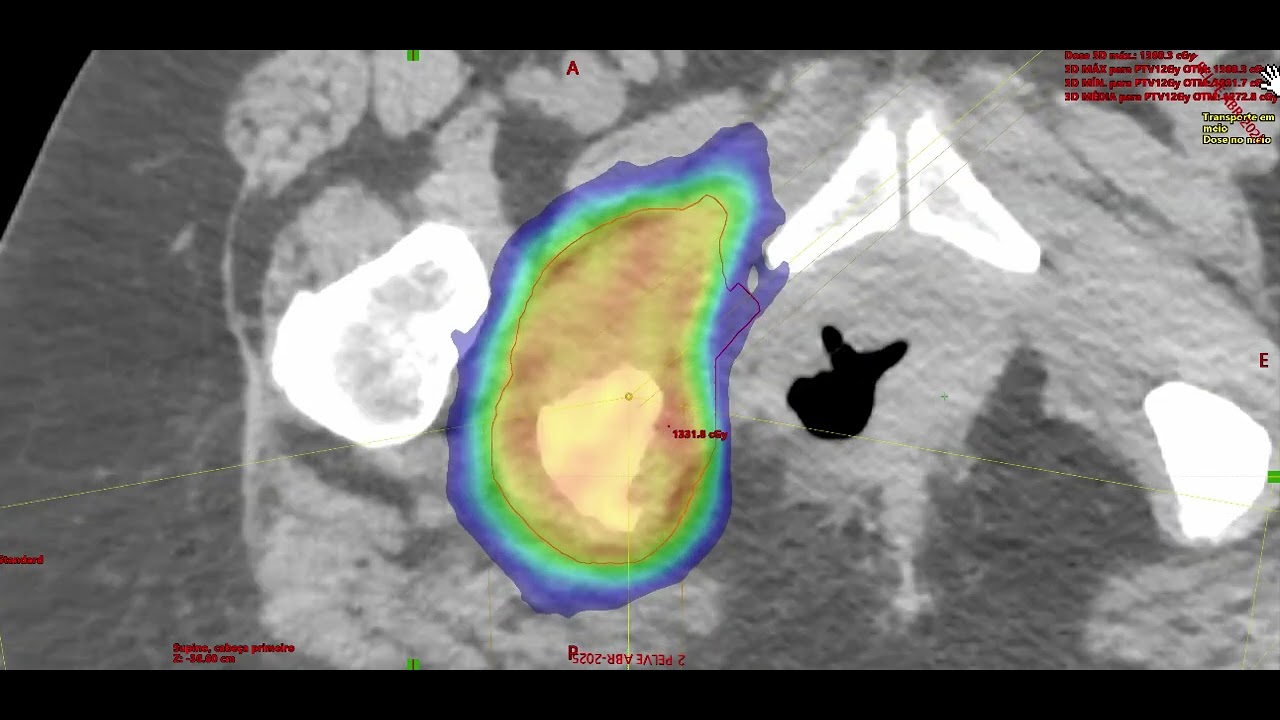

Tem interesse amplo em radioterapia, com familiaridade com diversas técnicas: Braquiterapia, Betaterapia, RT-3D, IMRT, IGRT, Radiocirurgia e SBRT. Tanto para o uso em tumores benignos e queloides, quanto, para tumores malignos. Tem interesse em de formas de minimizar toxicidades relacionadas à radioterapia e ampliação do cuidado em dor.

No tratamento oncológico é reconhecido pela sua capacidade técnica e qualificação, tem interesse em cânceres do Trato Gênito Urinário, principalmente, Câncer de Próstata e Cânceres Ginecológicos, tumores da Mama e do Pulmão. Atuou em São Paulo/SP, nos Hospitais: Beneficência Portuguesa, Santa Catarina - Paulista e Santa Paula e, ainda, como coordenador médico do Hospital Vitória - Santos/SP.